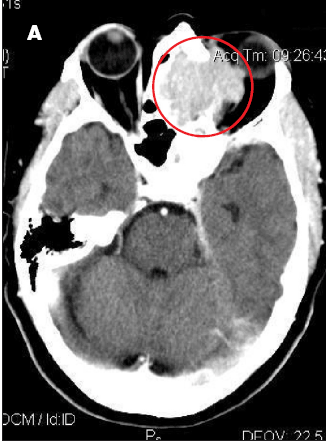

A 37-year-old man was brought to the emergency department (ED) after he had 2 near-syncopal events. The first occurred in the morning and rapidly resolved; the second occurred later in the day at work. The night before he had a headache and neck pain. In the ED, he reported left arm and leg weakness and was noted to have left facial droop.